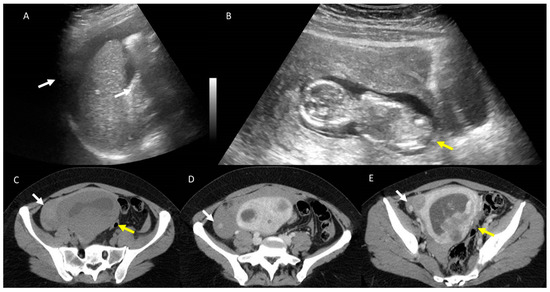

Background and Clinical Significance: Advanced pelvic organ prolapse (POP) associated with perineal herniation of pelvic and abdominal organs is a sporadic occurrence in gynaecological practice. Generally, POP affects up to 50% of multiparous women at some point during their lives. Advanced forms (grade III or IV) represent less than 10% of all cases, with severe grade IV prolapse occurring in fewer than 2% of patients. Case Presentation: We report the case of a 48-year-old nulliparous woman with no prior surgical history and no known medical conditions at presentation. The patient presented with severe grade IV POP (Baden–Walker Classification), characterised by abdominal pain, vaginal bleeding and significant urinary incontinence. A computed tomography scan was performed, revealing an extremely large perineal hernia, containing the uterus, urinary bladder, and small bowel loops—a rare finding with only isolated cases reported in the medical literature. Surgical treatment involved a total intracapsular hysterectomy with right-sided adnexectomy and colpoperineorrhaphy. After the surgery, the overall status of the patient was good. However, less than two months later, she returned, complaining of a recurrence of the initial pathology, and was diagnosed with grade II/III POP recurrence despite having no connective tissue disorders or other classical predisposing factors such as pregnancies, pelvic surgery history or obstetric trauma. The case was further complicated by a femoral neck fracture, stage V chronic kidney disease, COVID-19 pneumonia, and a Clostridium difficile infection. All these complications led to the postponement of the gynaecological reintervention procedure. Conclusions: We emphasise the significant challenges in managing this kind of perineal hernia, under unusual conditions and without common risk factors. A personalised, multidisciplinary approach is required, including careful follow-up to prevent early recurrence. Full article

Show Figures

Figure 1